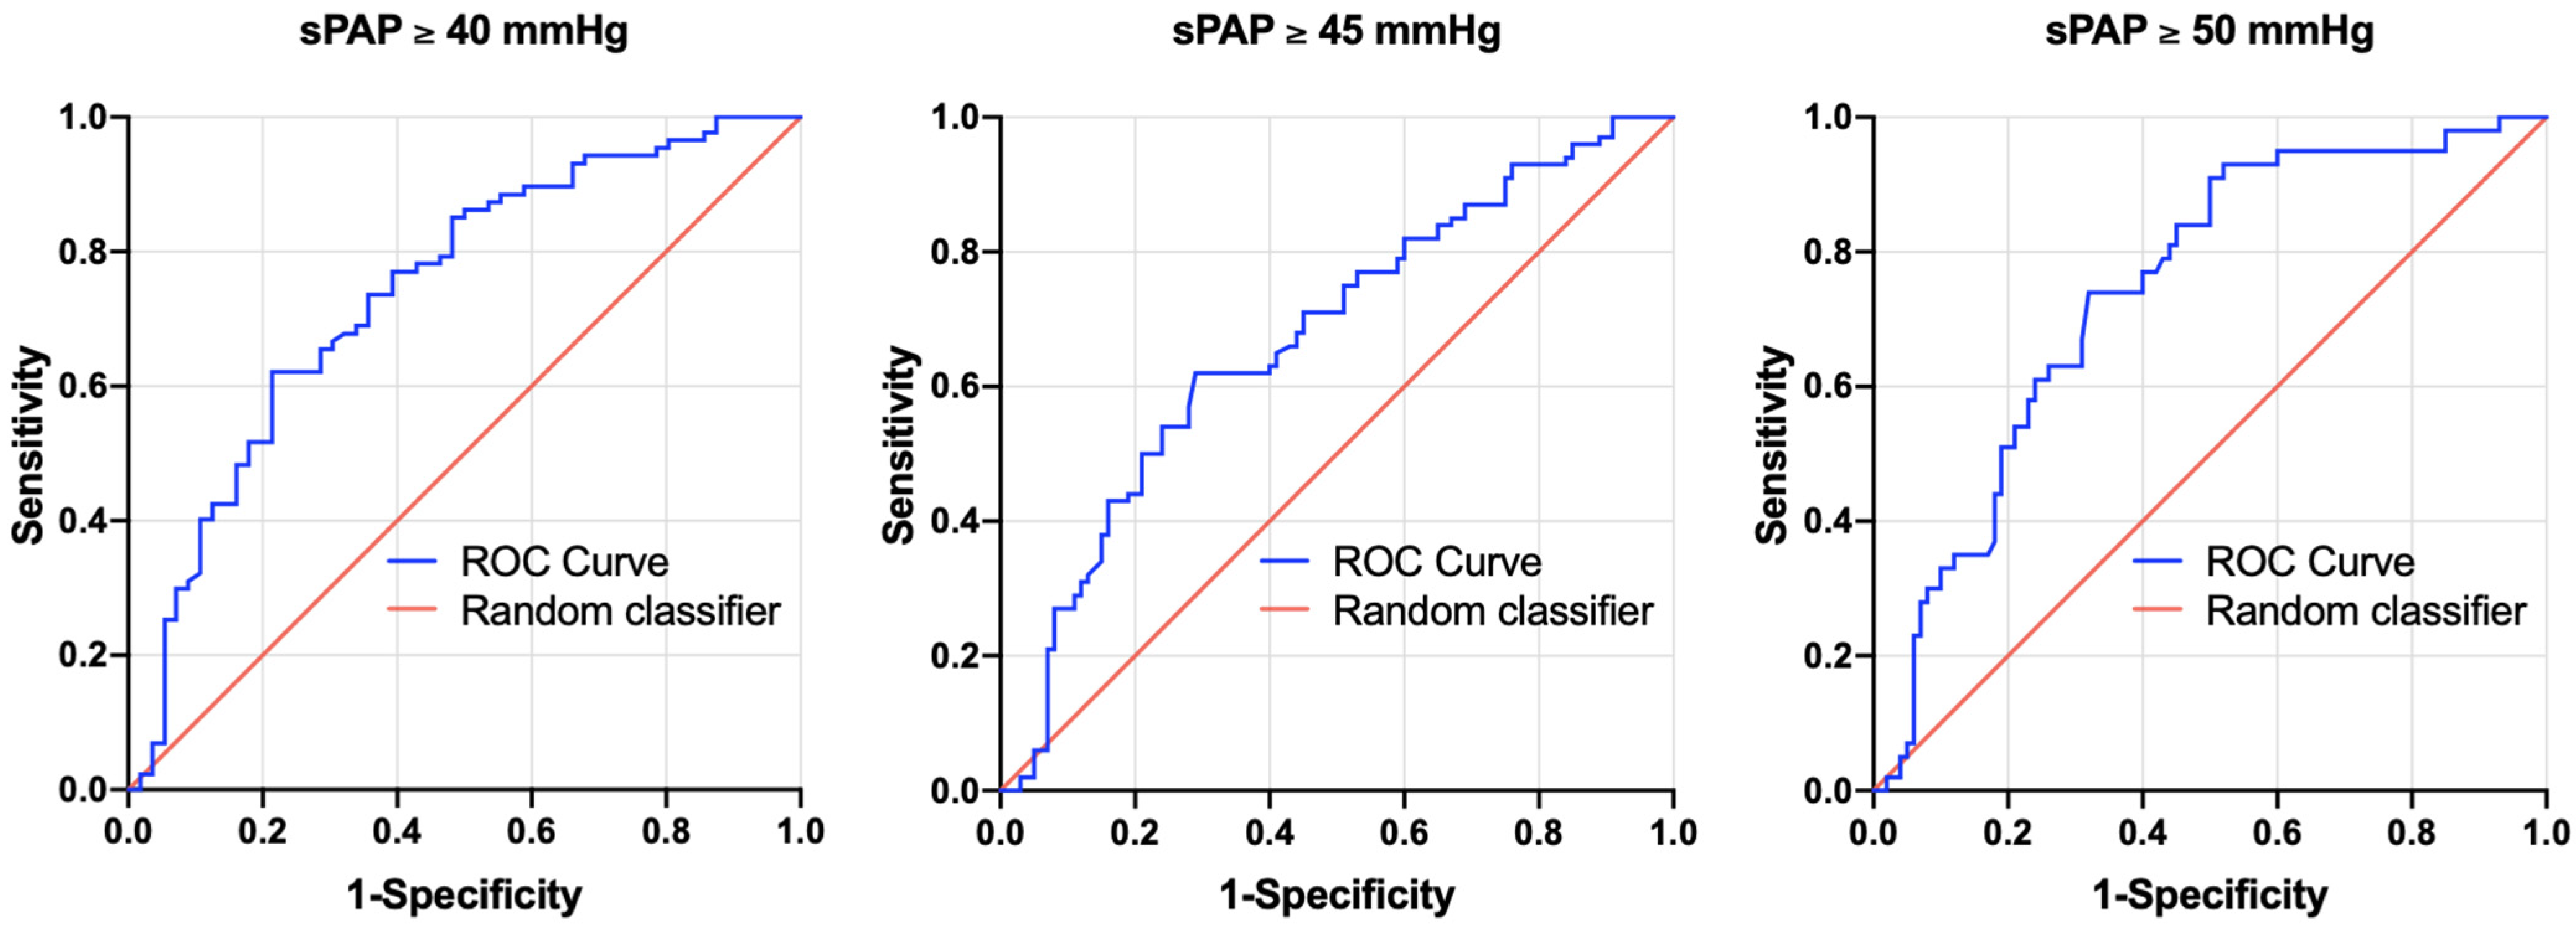

3.4. AUROC Results—sPAP vs. PA/BSA Ratio

3.5. Biomarker Concentrations in the Study Cohort

4.1. Can a PA/BSA ≥ 16.6 mm/m2 Be Used as Evidence for PH?

| PA/BSA (mm/m2) | sPAP ≥ 40 mmHg | 0.741 | 0.656–0.826 | <0.001 | 16.53 | 0.62 | 0.79 | 0.41 |

| PA/BSA (mm/m2) | sPAP ≥ 45 mmHg | 0.642 | 0.584–0.761 | <0.001 | 16.65 | 0.62 | 0.71 | 0.33 |

| PA/BSA (mm/m2) | sPAP ≥ 50 mmHg | 0.742 | 0.658–0.826 | <0.001 | 16.65 | 0.74 | 0.68 | 0.42 |